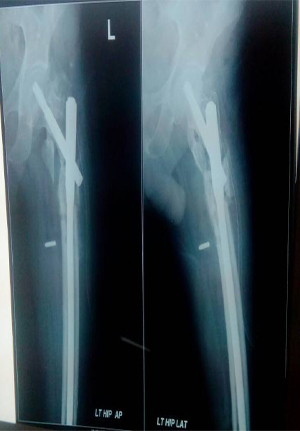

Proximal femoral nail for comminuated subtrochanteric fracture